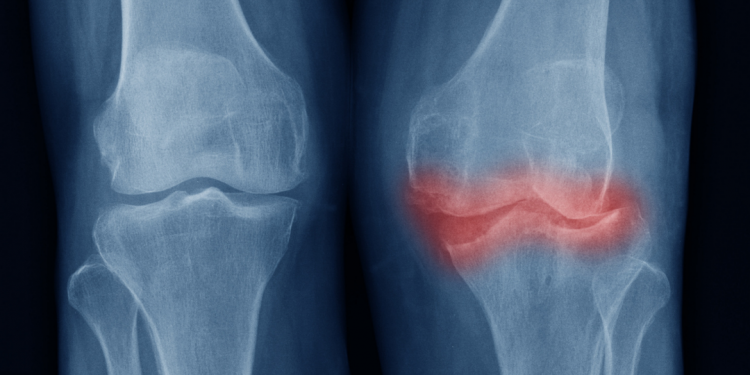

Você sabe o que é osteoartrite? Essa doença reumática é também conhecida popularmente como artrose ou osteoartrose. Muitas pessoas acreditam que se trata de um processo natural do envelhecimento. No entanto, a osteoartrite é uma doença causada pela insuficiência de cartilagem no corpo, acarretando em alterações nos membros acometidos.

No entanto, somente 30 a 50% dessas pessoas queixam-se de dor crônica. A osteoartrite se caracteriza pelo desgaste da cartilagem e por alterações ósseas. Entre essas alterações, estão os osteófitos, conhecidos popularmente por bicos de papagaio.

Ainda, as alterações na radiografia geralmente não correspondem aos sintomas apresentados pela pessoa. Ou seja, uma radiografia pode mostrar apenas uma pequena alteração em um indivíduo com sintomas graves, ou então pode apresentar inúmeras alterações em uma pessoa com poucos ou nenhum sintoma.